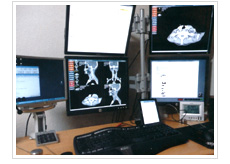

1. 高セキュリティかつコストパフォーマンスに優れたクラウドネットワーク

MITTでは、医療情報の機密性を守るために、独自のセキュリティ対策を導入したクラウドベースのシステムを運用しています。診療情報や画像データは安全かつ効率的に取り扱われます。

また、サーバー設置型とクラウド型の両方に対応可能で、医療機関の規模やニーズに応じて柔軟に導入いただけるのが特徴です。ITインフラの負担を最小限に抑え、かつ全国どこからでも都市部と同等の精度で読影サービスをご利用いただけます。

3. 放射線診断専門医による迅速・正確なレポート

当社の遠隔読影は、放射線診断専門医によって行われます。CT、MRI、検診など、あらゆるモダリティに対応し、質の高い読影レポートをご提供いたします。

読影結果は通常、営業日ベースで24時間以内にお届けし、再読影・追加コメントにも柔軟に対応可能です。診断精度の高さと応答の速さで、診療現場の意思決定を強力に支援します。